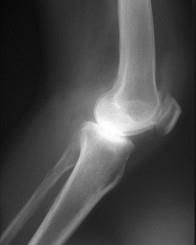

问题 女,56岁,手指关节肿胀,疼痛,僵硬,结合影像图像,选择最可能的诊断 ( )

选项 A、Reiter综合征 B、骨囊肿 C、类风湿关节炎 D、痛风性关节炎 E、关节结核

答案 C